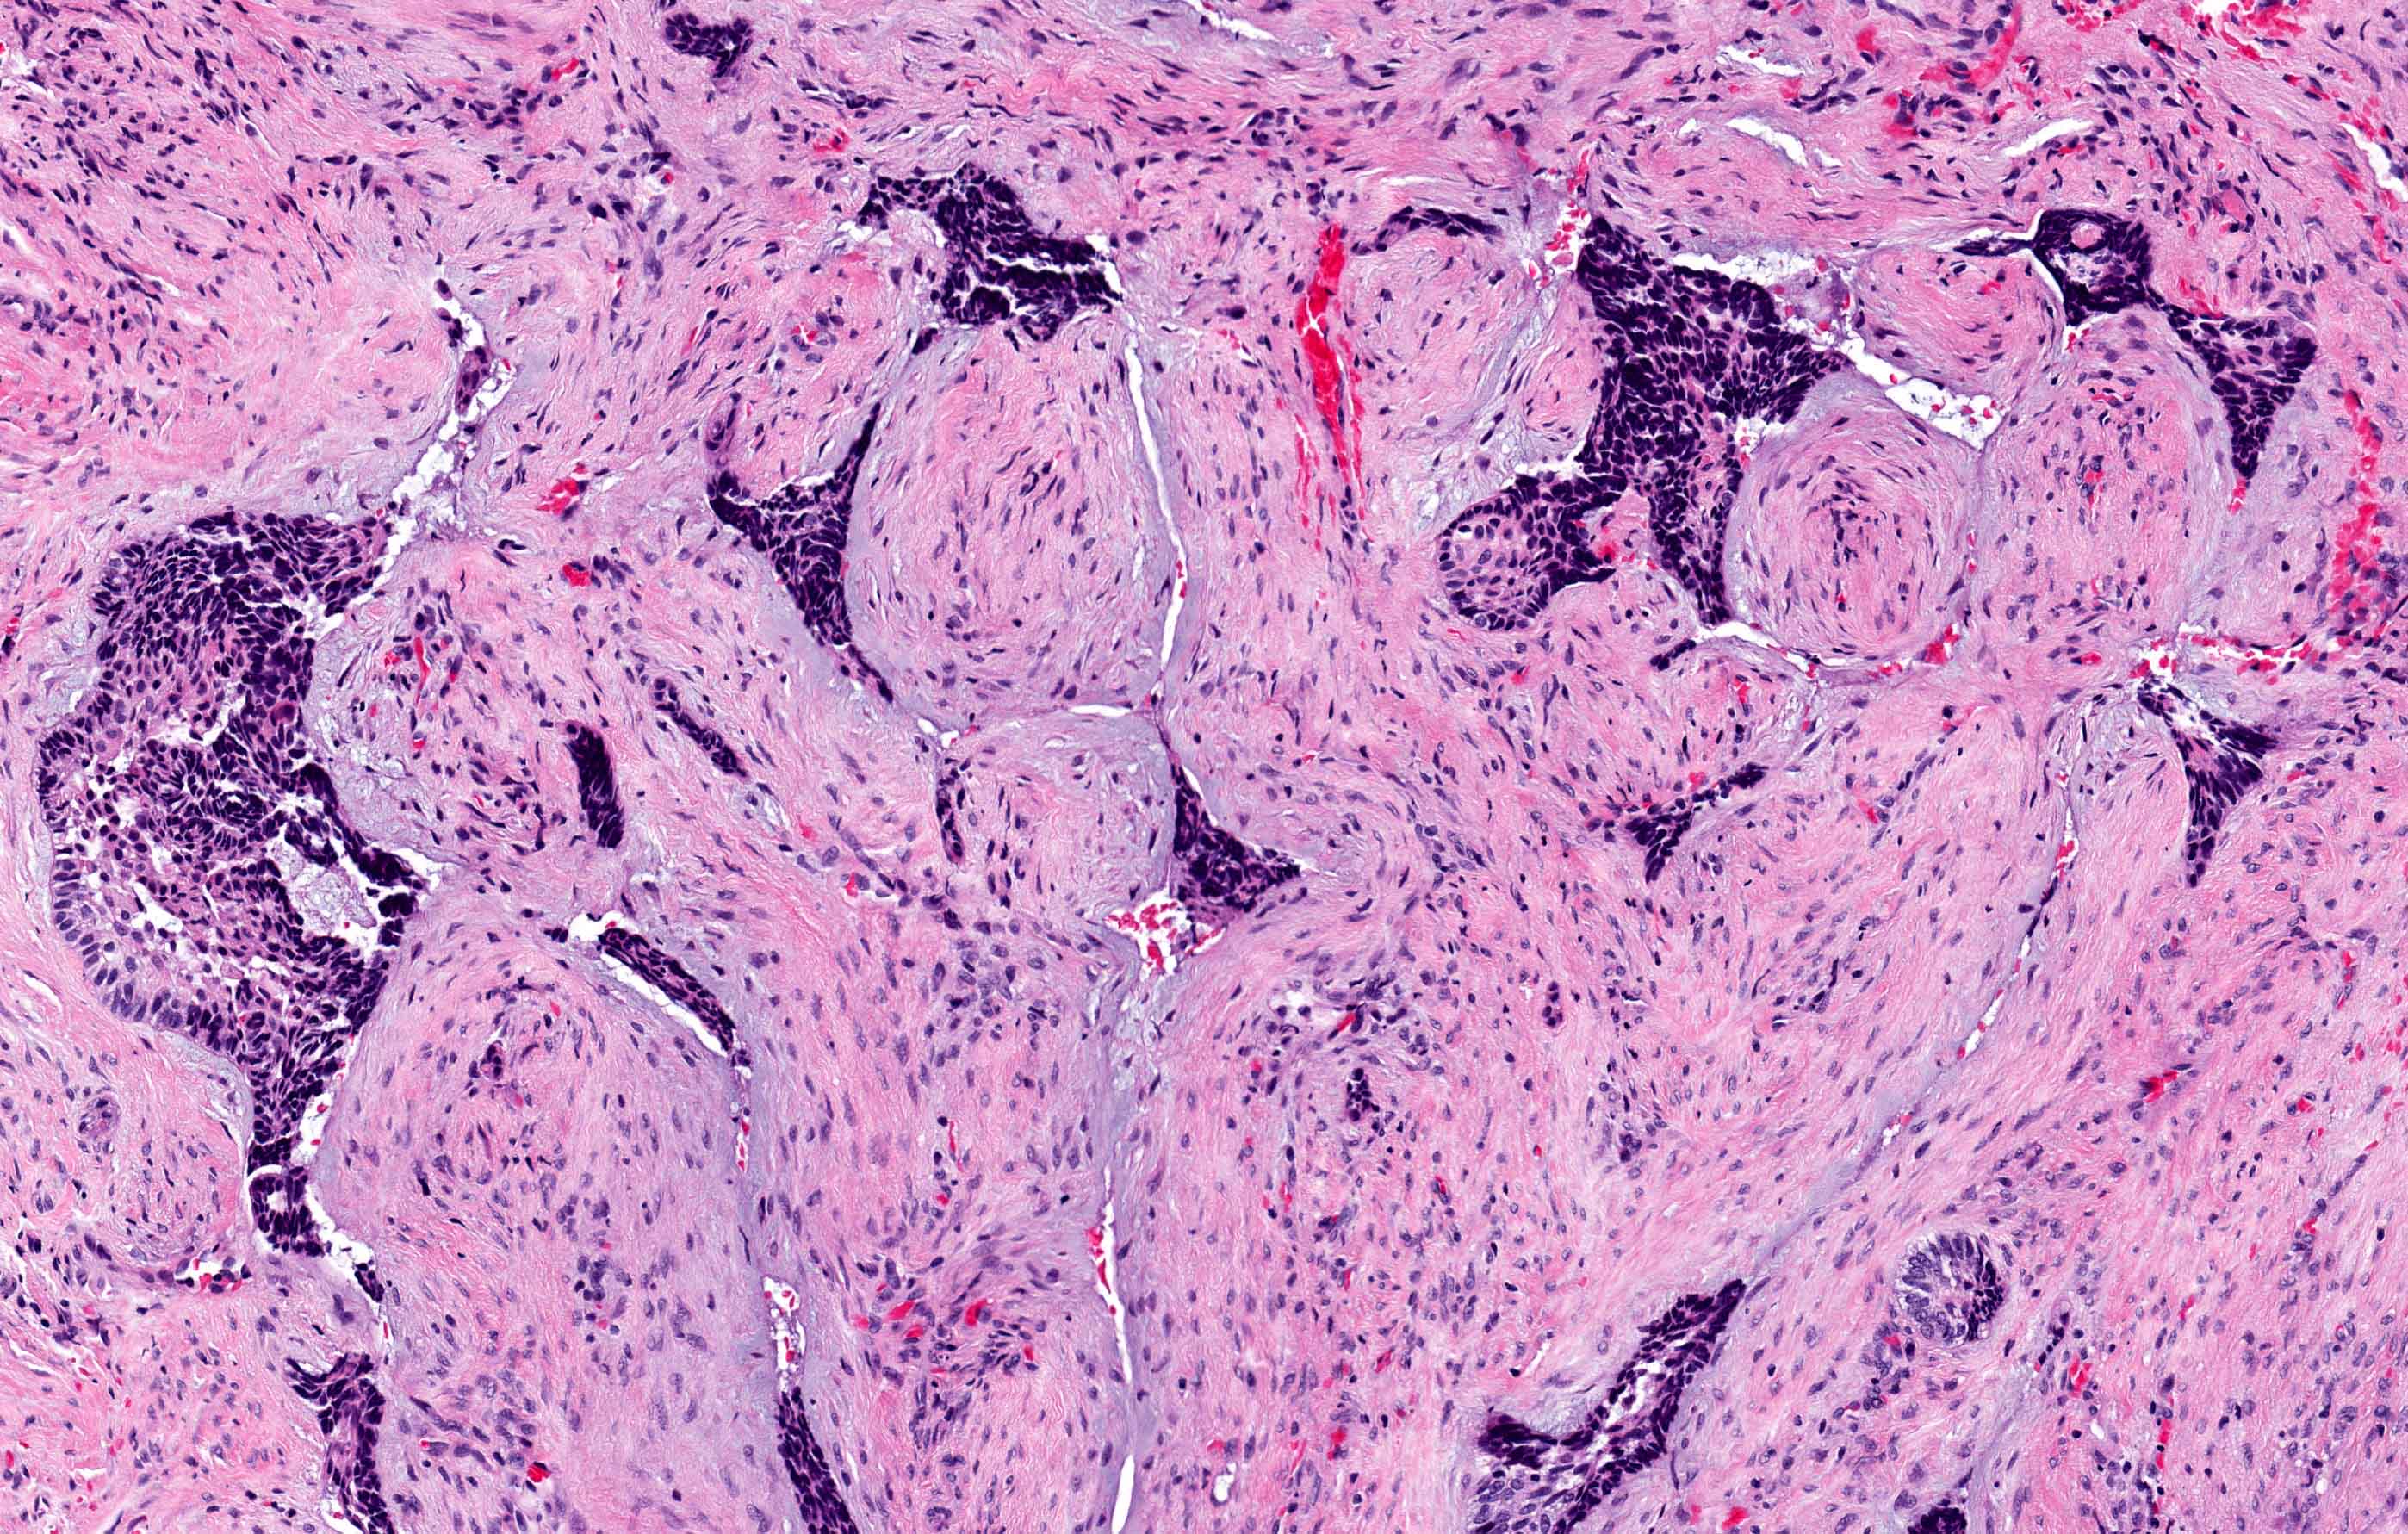

Microscopic (histologic) description

- Within the epithelial islands and cords of conventional ameloblastoma and the cystic epithelial lining of unicystic ameloblastoma, the odontogenic epithelium shows similar changes:

- Columnar cells with hyperchromatic nuclei at basal layer, exhibiting peripheral palisading

- Cells show reverse polarization away from basement membrane (Vickers-Gorlin change)

- Subnuclear vacuolization

- Suprabasal cells with a loose, network-like arrangement, recapitulating stellate reticulum formation seen in normal odontogenesis

- No dentin or enamel formation

- Desmoplastic: compressed and angular islands of epithelial tumor cells with dense moderately cellular fibrous connective tissue or collagenous stroma; the formation of metaplastic bone trabeculae is also described

- Ameloblastoma, unicystic type has 3 histopathological patterns

- Single cystic lesion lined by ameloblastic epithelium that shows typical features of ameloblastoma in some areas, including columnar basal cells in palisading arrangement with vacuolated cytoplasm, hyperchromatic nuclei polarized away from basement membrane

- Suprabasal cells loosely textured and noncohesive resembling stellate reticulum, epithelial invagination, epithelial edema and separation

- Microscopic variants (may result in treatment differences - controversial)

- Luminal: cystic odontgenic epithelium with characteristic features (above) lining fibrous connective tissue wall

- Intraluminal: cystic odontgenic epithelium with characteristic features (above) lining fibrous connective tissue wall, with tumor extending into the cystic luminal space; may have intraluminal plexiform patterns

- Mural: cystic odontgenic epithelium with characteristic features (above) lining fibrous connective tissue wall but with the additional finding of definite ameloblastoma tumor islands within the fibrous connective tissue wall

Microscopic (histologic) images

Contributed by Kelly Magliocca, D.D.S., M.P.H. and Anne C. McLean-Holden, D.M.D., M.S.